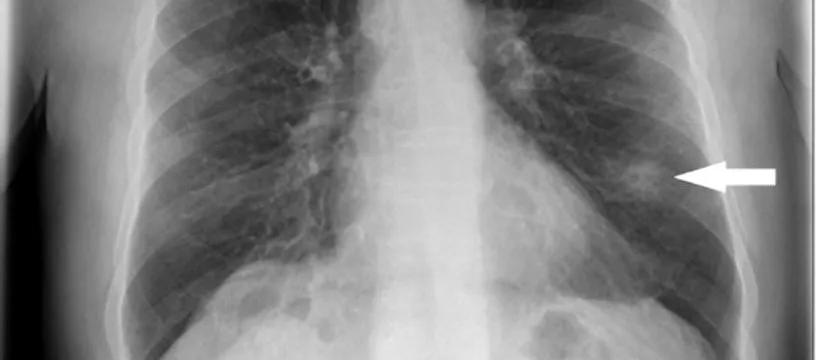

Kanaan博士:从定义上看,肺结节是指直径在3厘米以内的类圆形或不规则型病灶,而大于3厘米的病灶则称为肺肿块。在成像测试描述中,肺结节通常被称为“硬币病灶”。其中,磨玻璃样结节(GGO)是较多发生在亚洲人群的一种结节形态,表现为密度轻度增高但又没有遮住支气管血管,仿佛在肺部组织上蒙上了片磨玻璃的云雾状淡薄影/圆形结节。

Kanaan博士:根据美国Fleischner学会2017年发布的《肺部CT偶发性结节管理指南》,要从影像上判断肺结节有没有癌变可能,需要结合其大小、密度,以及在磨玻璃样结节的中央有无高密度影像、有无空炮征象及血管征象等来分析。

判断肺结节良恶性,不能光看大小

海军军医大学长征医院影像医学科原主任、我国放射学界第一位博士、有着“神眼”之称的肖湘生教授认为,肺结节的大小并不能证明它是良性还是恶性,需要通过严密的影像学诊断作为依据,给出对应的判断。